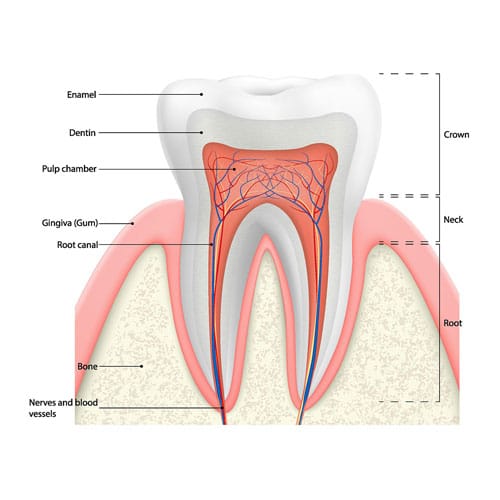

ROOT : This part of the tooth sits in the bone below the gum. The root of your tooth is usually

twice as long as the crown, the part you see above the gum line.

The pulp is the living tissue of the tooth with blood supply and nerve supply. Once dental caries (decay ) involves the pulp, the pulp gets infected causing pain. The aim of the root canal treatment is to remove the infected pulp. This is done by removing the infected pulp with files in the pulp chamber and cleaning and shaping the root canals and sealing the canal with a filling material. At Anbu Dental Clinic, we provide the best root canal treatment at an economical cost in whole Madurai city. “PRESERVING YOUR TOOTH FOR YOUR FUTURE”.

Root canal therapy

Each tooth has a soft tissue – the pulp which nourishes the tooth. Because of deep decay, injury, or gum disease, the pulp tissue in your tooth has become inflamed or infected. In any other part of your body, if a similar tissue becomes diseased, the body merely throws it off and forms new tissue. However, a tooth is a unique and different. Because the infected soft tissue (pulp) within the tooth is totally encased within hard tissue, it is the role of the dentist to remove the soft tissue located in the root canals, cleanse the area, and finally fill the canals with a special material so that bacteria cannot re-enter the tooth to cause another infection. When the endodontic treatment is complete, the tooth is by no means “dead”. It receives quite adequate support from the surrounding tissues and may be expected to last as long as any other natural tooth.